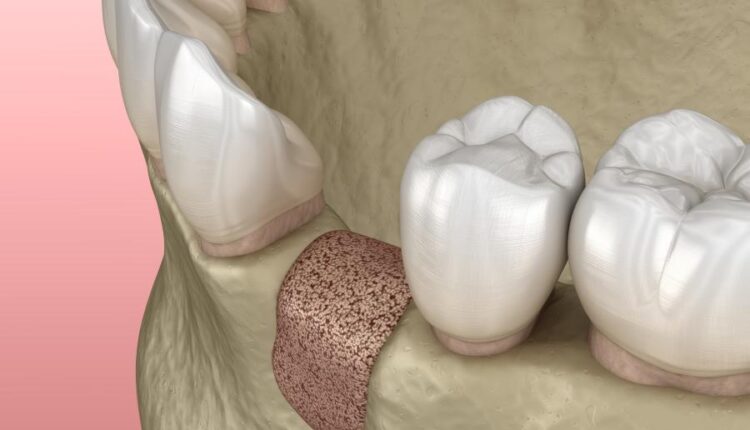

عکس استوک دندان و دندان پزشکی سه بعدی – Treatment of tooth 3d

مراکز و کلینیک های دندان پزشکی برای بردهایی که برای بیماران در محل قرار داده اند یک سری موارد تبلیغاتی و اینفوگرافیک طراحی می کنند که در آن مراحل درمان بیماران را با تصویر و اطلاعات کنار آن نشان می دهند. این تصاویر استوک دندان و دندان پزشکی سه بعدی بسیار می تواند برای طراحی این اینفوگرافیک ها مورد استفاده قرار گیرد.

نمونه عکس های استوک دندان و دندان پزشکی سه بعدی :